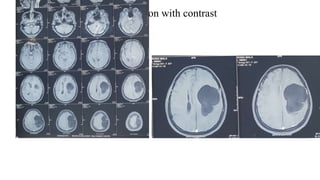

MRI of the brain with contrast

MRI of thebrain with contrast

• #41 Plain CT scan of Head revealed Smooth bordered non calcified cystic lesion with single septation in left frontoparietal region with density similar to CSF with crowding of adjacent sulcus & gyrus, effacement of adjacent lateral ventricle and slight midline shifting Rest of the brain parenchyma, bony calvaria is normal. No extracalvarial lesion is visible.

• #43 MRI of brain T1WI multiple axial sections showing a well defined fairly large lesion measuring 7.5cm * 4.5cm in diameter, smooth bordered homogenously hypointense lesion in left frontoparietal region with intensity similar to CSF. There is crowding of adjacent sulcus & gyrus and effacement of adjacent lateral ventricle and slight midline shifting Rest of the brain parenchyma is normal. No extracalvarial lesion is present.

• #44 T2WI shows the lesion is homogenously hyperintense.

• #45 Sagittal image shows the lesion compressed and distorted the lateral ventricle.

• #46 In coronal view the lesion pused the adjacent to left lateral ventricle medially and inferiorly.

• #47 FLAIR image shows the lesion is homogenously hypointense

• #48 No restriction; nearly identical to ventricles Diffusion restricted –pheriphery –neoplasm Centrally-radiation necrosis

• #49 Contrast enhanced axial MRI shows there is no contrast uptake by the lesion and also there is no ring enhancement

• #50 Contrast is not uptaken by the lesion.